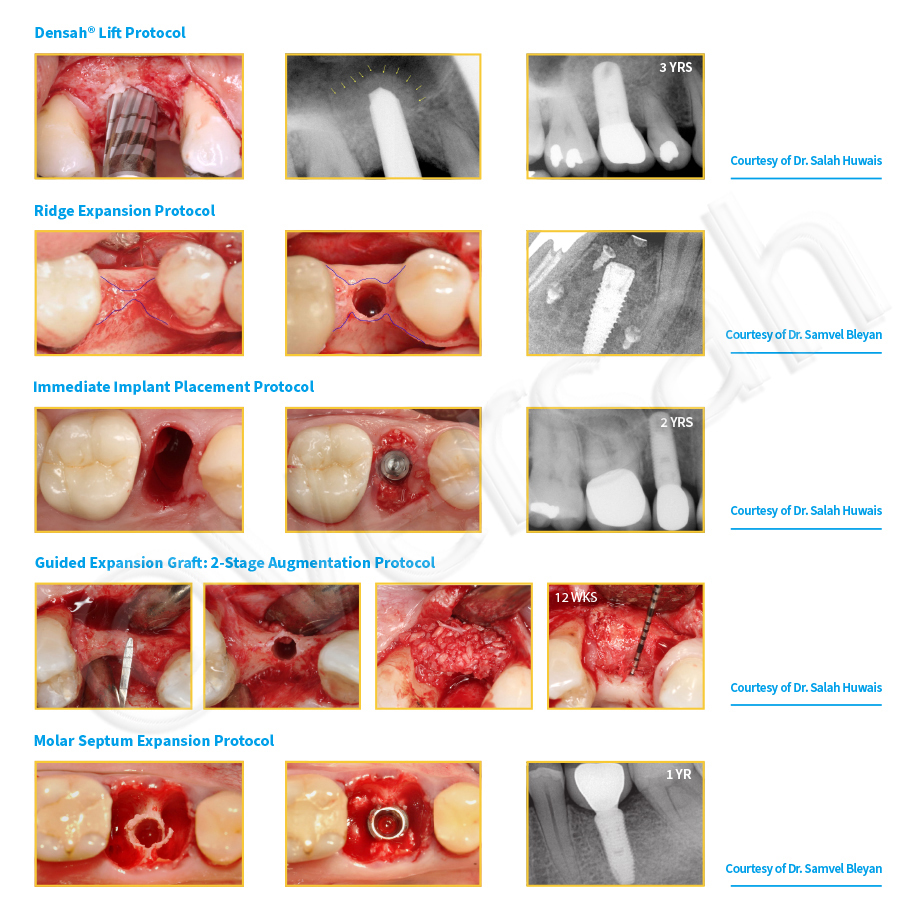

Clinical Cases